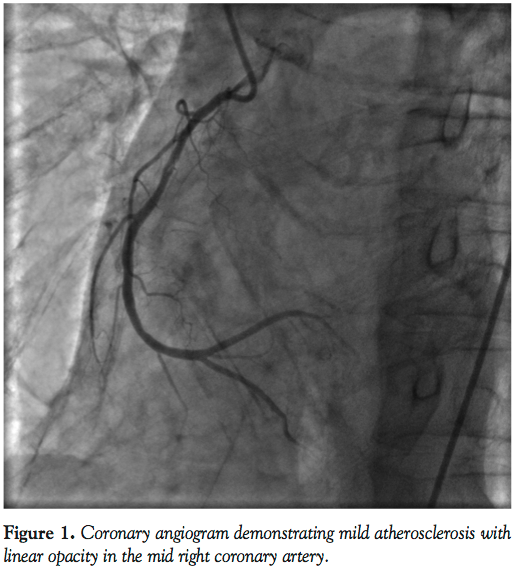

The patient is a 62-year-old man with hyperlipidemia, who was admitted with acute exacerbation of chronic obstructive pulmonary disease needing mechanical ventilation and support with cardiac pressor. He sustained a non-ST elevation myocardial infarction with peak troponin at 1.2 ng/mL. Echo windows could not be obtained due to lung hyperinflation. After extubation 24 hours later, he underwent cardiac catheterization. Angiogram demonstrated only mild atherosclerosis with non-flow limiting linear opacity in the mid-segment of the

right coronary artery (RCA), and mildly reduced ejection fraction with inferior wall hypokinesis. The finding was initially thought to represent spontaneous RCA dissection or intracoronary thrombus (Figures 1 and 2) or calcification. A Prestige Plus FFR wire (Volcano Corporation) was passed carefully beyond the linear opacity. There was mild resistance encountered while advancing the body of the wire. FFR was 0.73. To further delineate the opacity, optical coherence tomography (OCT) was